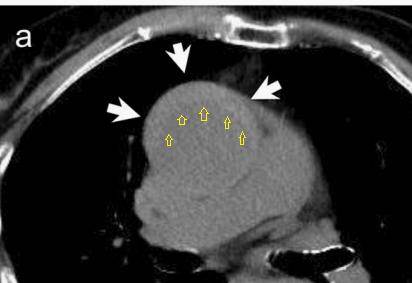

增强CT一看,主动脉夹层,密度相对高的是流动的血液!

下图的胸部CT平扫,基本上大约肯定可以看到一条线样阴影,将主动脉一分为二!

增强CT一看,主动脉裂开了!